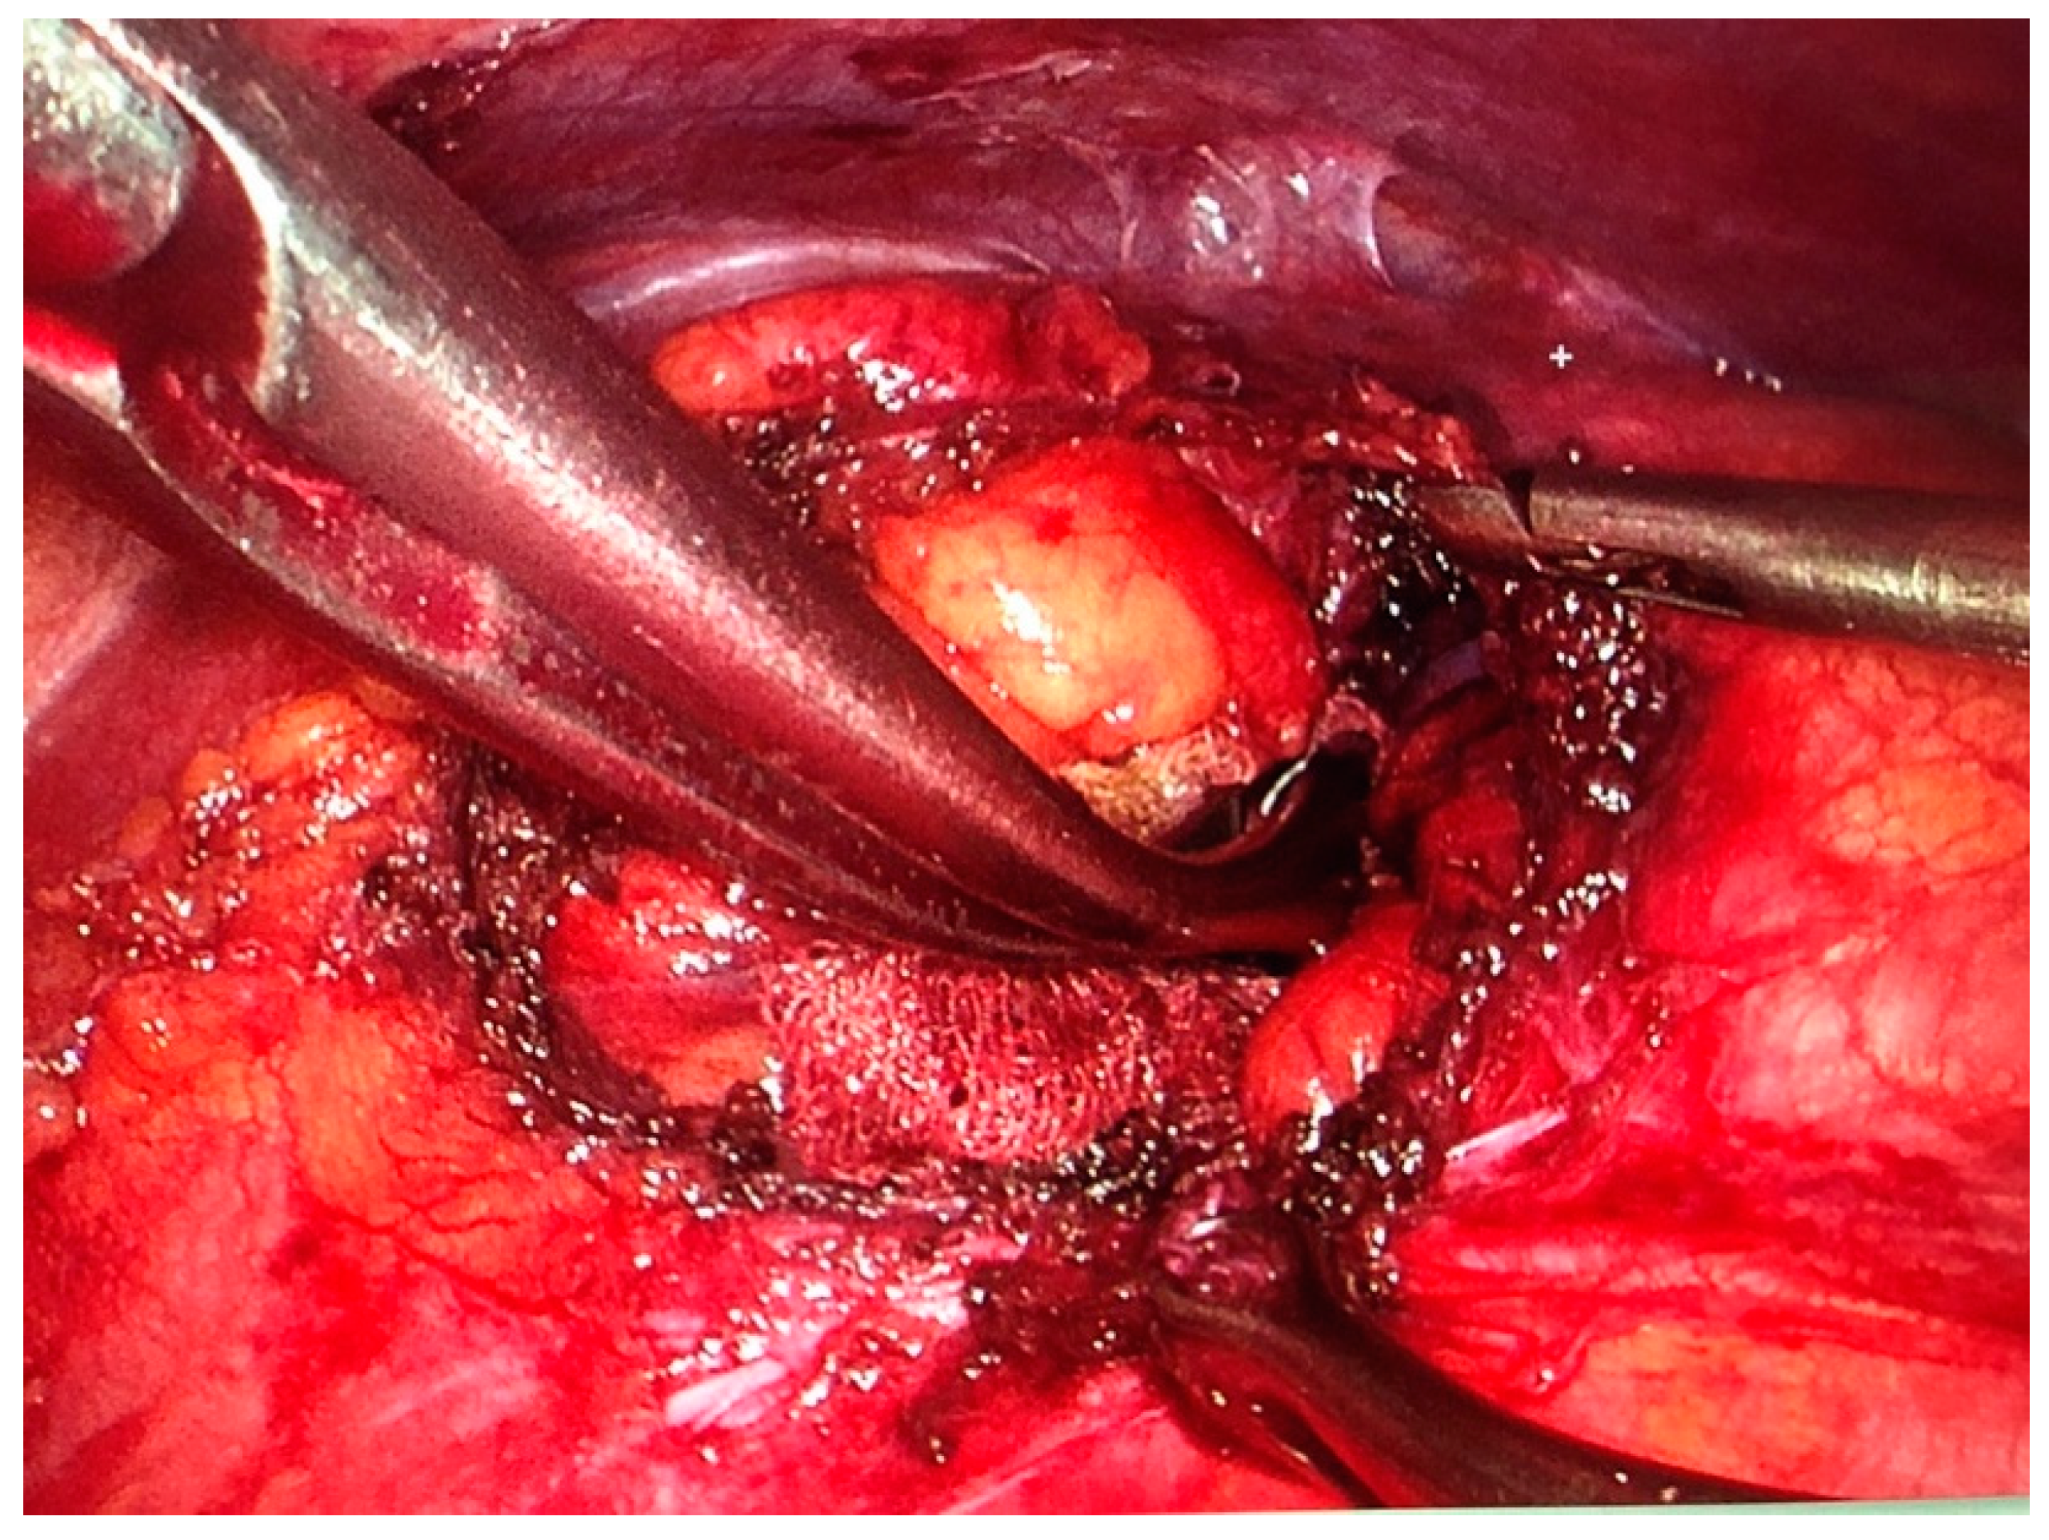

We performed a VATS procedure. The patient was placed in the right lateral decubitus position. A 5 mm 30-degree thoracoscope was introduced through a 5 mm trocar placed in the 4th intercostal space on the anterior axillary line. After exploration of the pleural cavity and identification of the hernia, two 10 mm trocars were placed in the 7th intercostal space on the mid- and posterior axillary line, respectively. Two additional 5 mm pleurotomies were performed in the 9th intercostal space on the posterior axillary line, and in the 6th intercostal space on the anterior axillary line. After reduction of the hernia, the defect was measured as 3.5 cm in diameter (Figure 3). The hernia consisted of left transverse colon that was contained in a hernial sac. It was dissected and reintegrated in the abdominal cavity. Next, the defect was closed with simple interrupted stitches of a nonabsorbable, braided suture (Ethibond 0) (Figure 4). The suture line was reinforced with a 12 cm diameter polyvinylidene fluoride (PVDF) mesh (DynaMesh®-IPOM) that was anchored with four stitches of nonabsorbable polypropylene sutures (Prolene 2-0) and surgical glue (IFABOND®) (Figure 5). We placed one chest tube (28 Fr.) with suction (−20 cmH20) at the end of the procedure. There were no intraoperative complications. Operative time was 170 min.

Figure 3.

Diaphragmatic breach, with hernial sac dissected and pushed back in the abdominal cavity.